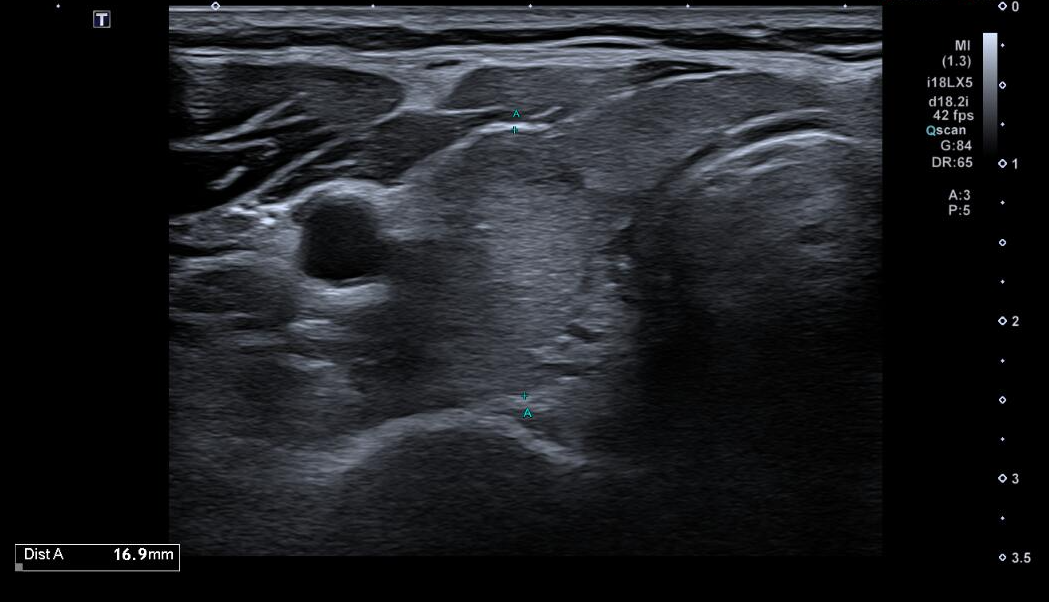

Tras dichos hallazgos, se decide realización de Ecografía Clínica.

Ecografía clínica:

Ecografía reglada (Servicio de Radiología):